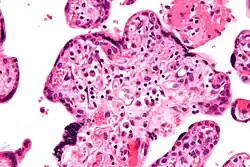

| Micrograph of villitis of unknown etiology, a placental pathology associated with IUGR. H&E stain. | |